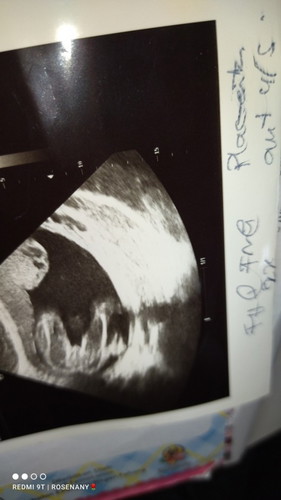

Jom mummy teka jantina bayi.. mengikut pengalaman mummy semua bedasarkN gambar ni mummy rasa boy @ girl😍

kena npk punai dlu br tau jantina ape..tp npk cmni je mcm girl..sbb xnpk punai...mcm sy scan 6bln btl2 npk telur bulat sgt2 sbb tgk dr bwh..doc pun ckp npk mcm boy...punai xnpk sbb terlindung dek tali pusat..tp 2mgu lg scan btul2 buger mksdnye girl la..sbb xde punai..

macam girl sebab tak besar sangat yang celah paha tu😅 sy haritu nampak jelas terus....be careful kalau scan tak jelas...risau kena prank dekat baby😅

mcm boy sbb nmpak kembung mcm telur dia je

sya berhrp girl... 😄 sebb doc katA xnmpk batu nyer... humburger dia xberapA chubby lg ..